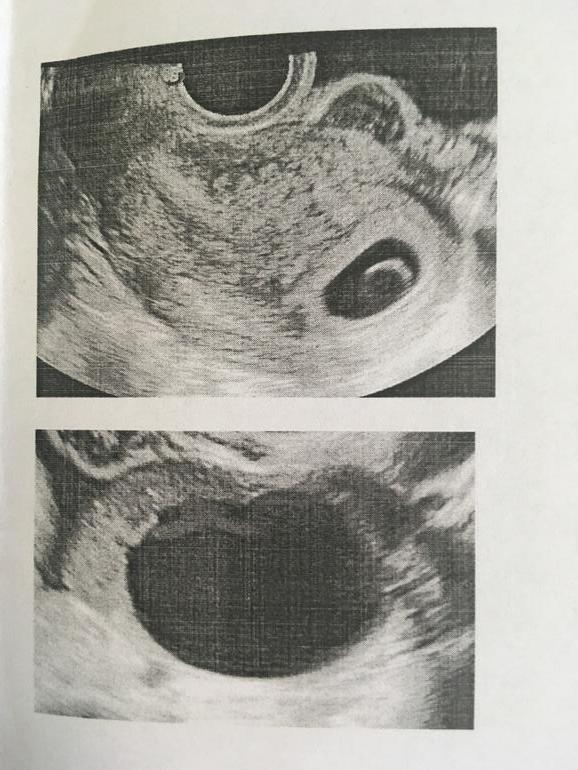

Первая и долгожданная беременность, последние месячные были 20 марта. Сегодня 13 мая на УЗИ дали такое заключение. Срок 6 недель 5 дней, Эмбрион не лоцируется. Но желточный мешок есть, 8,5 мм. Стоит ли надеются что эмбрион появиться спустя неделю? Анализы ещё не сдавала. Собираюсь к геникологу 15 мая.